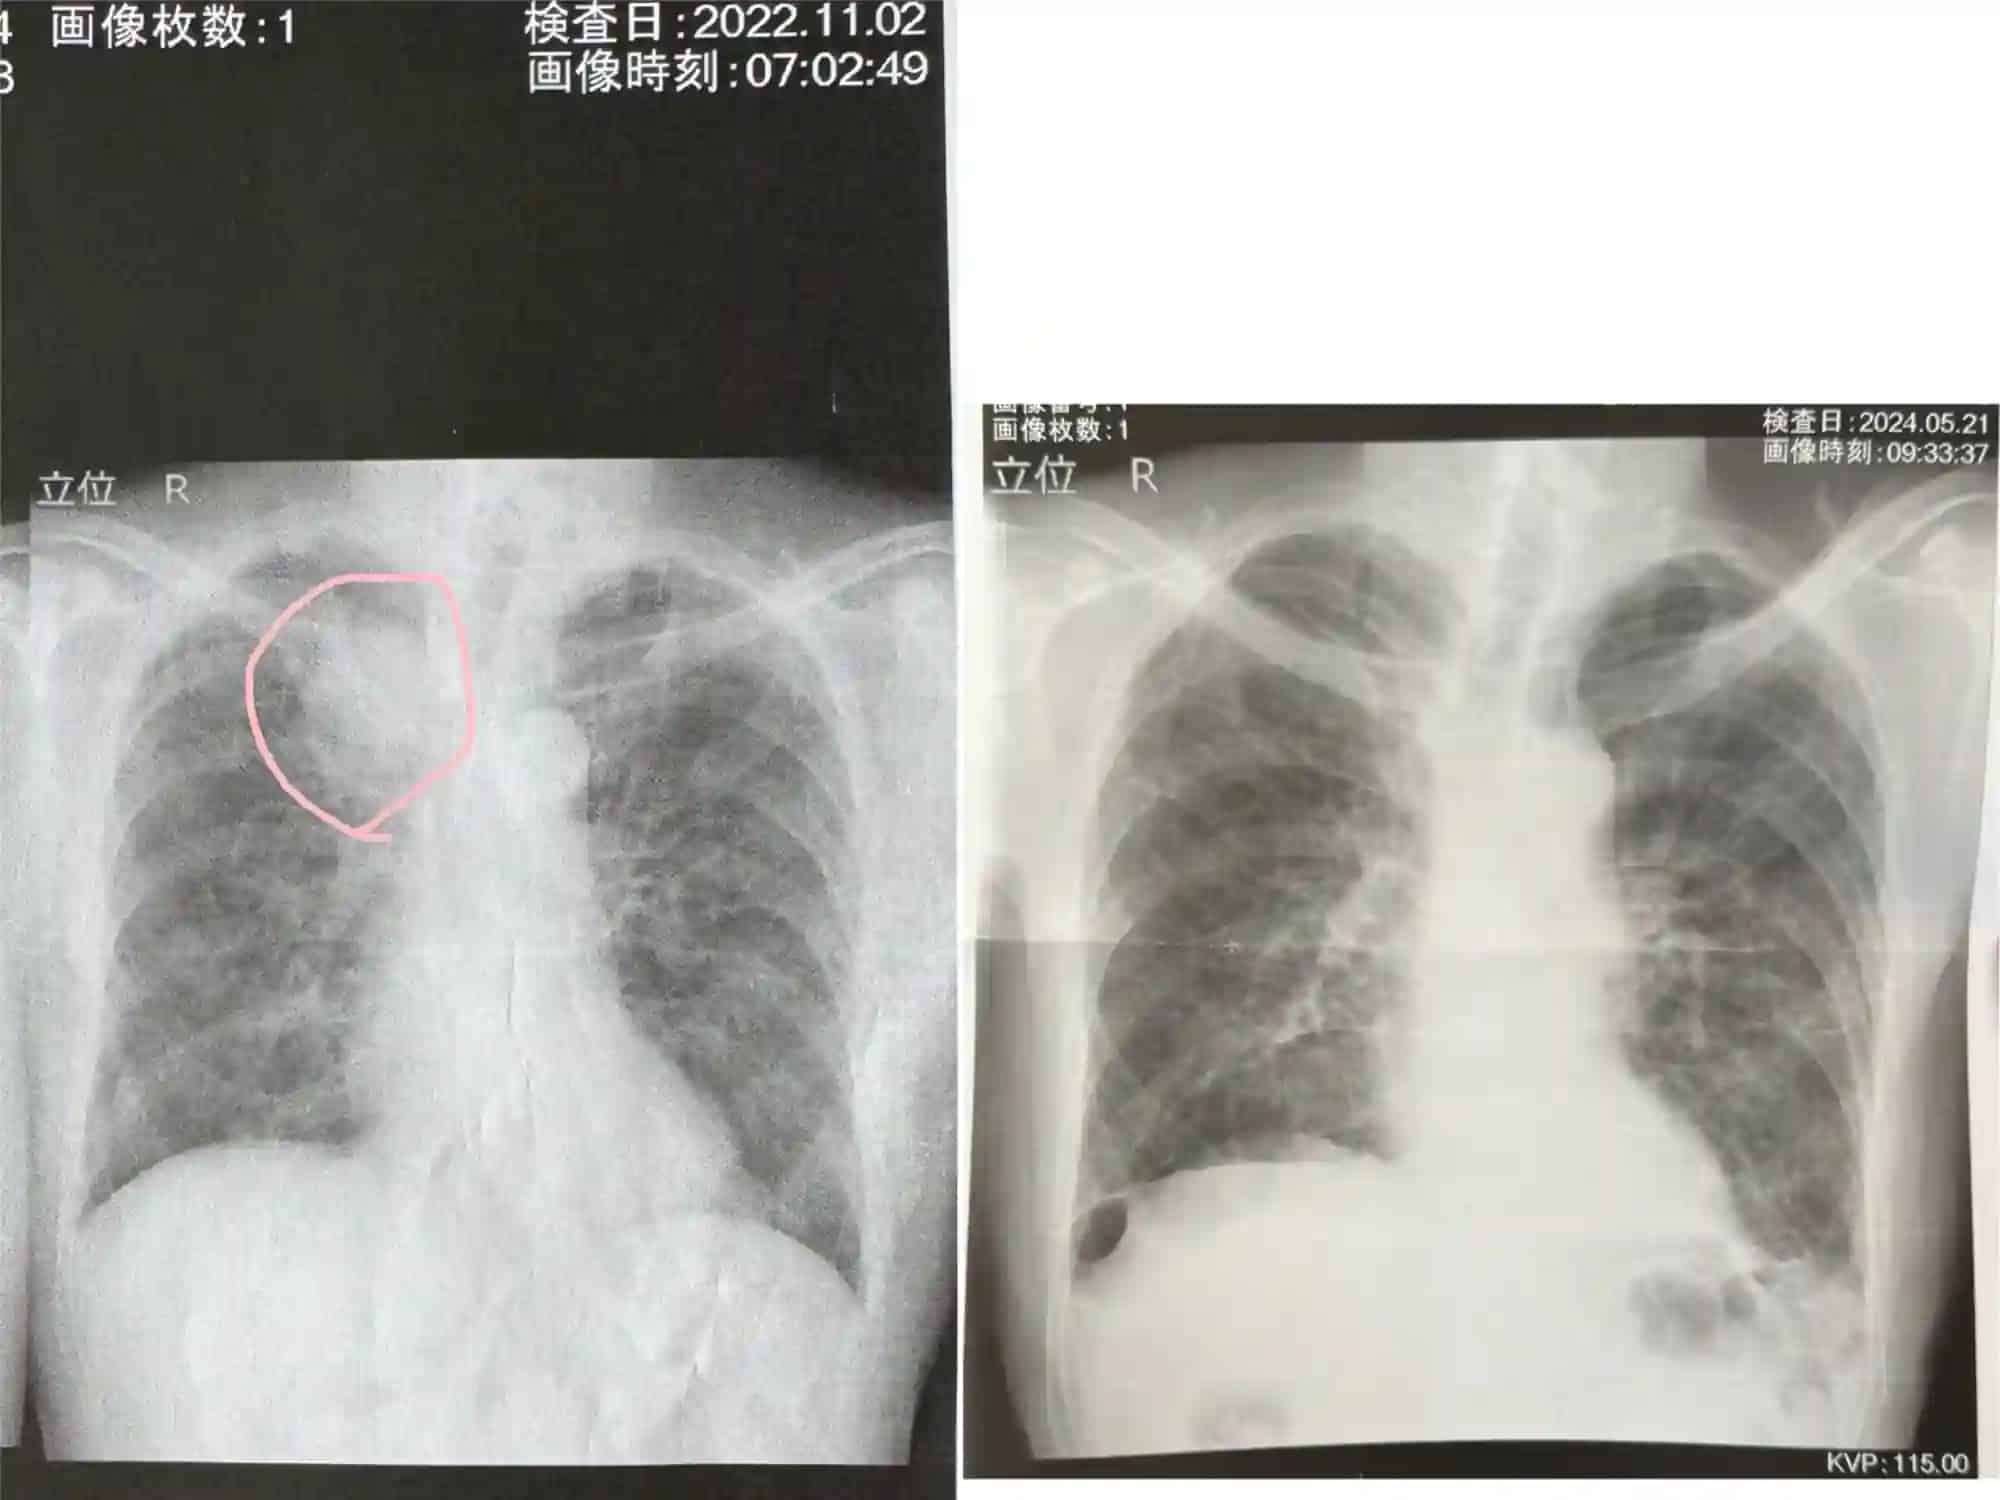

ทว่าเรื่องราวไม่ได้จบเพียงแค่นี้ เพราะเมื่อเร็ว ๆ นี้คุณพ่อของ @asobiworld ได้ไปโรงพยาบาลเพื่อตรวจมะเร็งอีกครั้ง ทว่าเจ้ามะเร็งระยะที่ 4 ที่ควรจะจบชีวิตของคุณปู่ในปีนี้ จู่ ๆ กลับหายไปเสียดื้อ ๆ! ซึ่งคุณ @asobiworld ได้แนบภาพเทียบภาพ X-Ray ปอดในปัจจุบันเทียบกับช่วงปี 2022 ตอนที่ยังมีก้อนมะเร็งอยู่ เพื่อชี้ให้เห็นว่ามันหายไปจริง ๆ

เห็นแบบนี้ก็นับได้ว่าเป็นเรื่องที่น่ายินดี จนคุณ @asobiworld อดคิดไม่ได้ว่าการได้มีโอกาสคอสเพลย์เพิ่มแรงใจร่วมกับหลาน อาจเป็นสิ่งที่ช่วยต่อชีวิตให้กับคุณพ่อของเขา และคิดไว้แล้วว่าจะถ่ายภาพคอสเพลย์ชุดต่อไปอีกเร็ว ๆ นี้ ขณะที่ชาวญี่ปุ่นหลายคนก็ให้ความสนใจกับโพสต์ของเขาจนมียอดวิวกว่า 10 ล้านวิว เรียกได้ว่าปาฏิหารย์นั้นมีจริง!